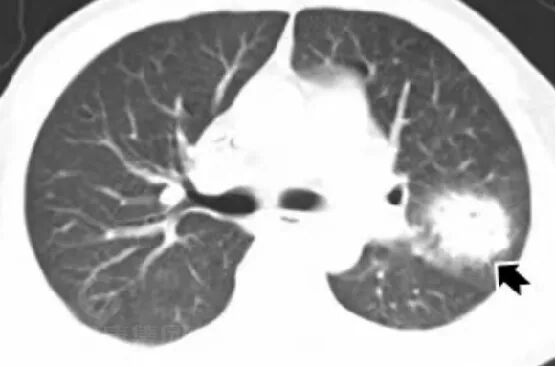

· 双肺多发结节、肿块,周围晕征

· 以胸膜下分布为主

影像学表现——晕征样结节和楔形实变影

早期出现多发密度增高的结节影,周围可见晕征。「晕征」表现为围绕结节周围的略低于结节密度而又高于肺实质密度的环行带状区,其病理基础是肺曲菌破坏肺部小血管,导致肺实质出血性坏死。「晕征」是 IPA 早期最具提示性的特征性 CT 表现,也是活性曲霉菌存在的标志, 见于 40~69% 的早期病例,高峰期为病变的第 5 天(1-30 天)。

晕征:凝固坏死+病变周围出血